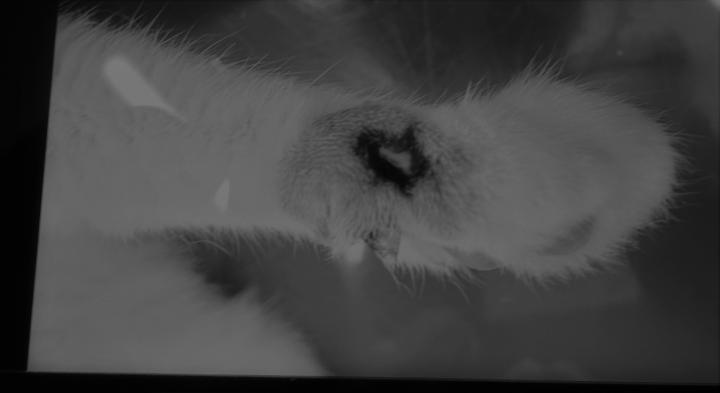

病院へ連れて行く数日前の写真。当日はもう少し狼爪の根元が変色していました。でも大きな傷は無し。

獣医に見せられた写真

「毛ぞりしたら骨も見えている状態だった」と。←嘘つきが!!と思ってしまいました。

爪が生えているところは毛ぞりしなくても見えているしあんな大きな穴になっていなかった

のは確かなんです。不信感がつのるのみですが病院を何箇所も連れ回したくないので穏便に。